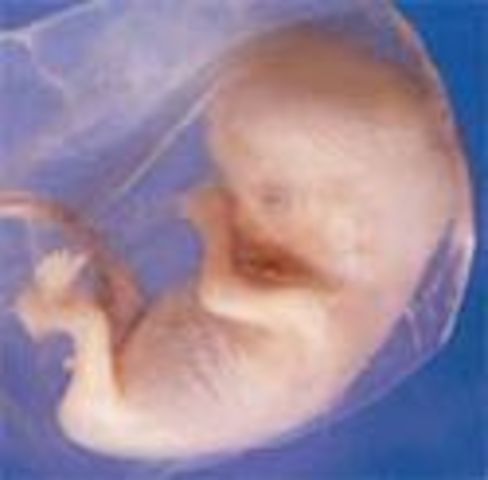

• Week 10: Embryo is Now a Fetus

Week 10: Embryo is Now a Fetus

The embryo is now called a fetus until birth. The fetus is the size of a small strawberry. The fingerprints are becoming evident in the skin and the nipples and hair follicles are forming as well.